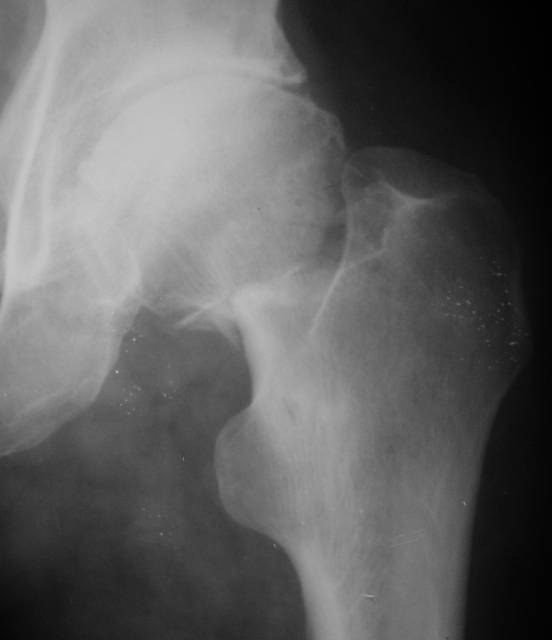

[Ortho] несросшаяся шейка бедра

Имя     : ex-fix.jpg

Url     : http://weborto.net:8080/pipermail/ortho/attachments/20070530/d5d32c11/attachment-0005.jpg